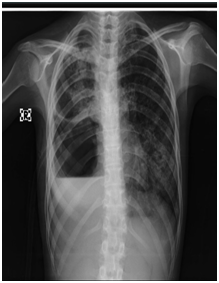

During follow up a mild fistula and pleural dead space happened, but PT clinically got better. After 5 months the fistula continued and the residual pleural cavity got bigger Figures C1–C6. The plan of management was depending on:

• At first day CXR reveal a consolidation in the lower third of the right chest and no residual cavity Figure D3